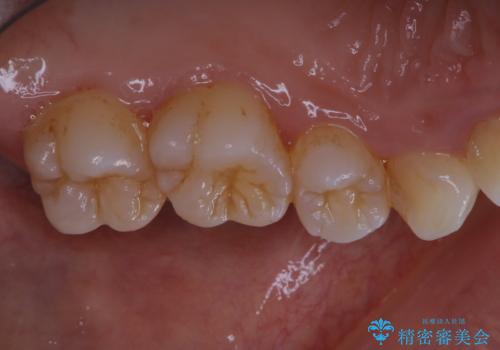

久々の来院で歯のクリーニング PMTC60分コース

- しばらく来院できなかったため、全体的にチェックとクリーニング希望でした。PMTC60分コースを行いました。

歯にステイン(着色)や歯石などが付着していると、汚れなのか虫歯なのかの判別が分かりにくく、正確な診断ができないことがあります。

そのため、定期的に専門的な機械や材料を使用したクリーニング(PMTC)をすることで、ご自身本来の歯の状態となります。より、健康なお口の維持をするためには、痛みや症状などが無くてもPMTCを行いお口の中の環境を綺麗にすることがおすすめです。